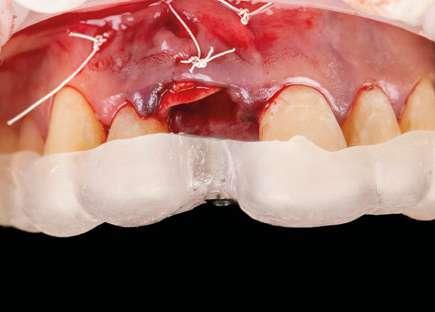

Cirugía

Con toda nuestra cirugía perfectamente diagnosticada y planificada solo nos queda ejecutarla. 1.- Quitamos la corona ferulizada.

EN IMPLANTOLOGÍA 20 eldentistamoderno mayo/junio 2024

2.- Extraemos de manera meticulosa la raíz del diente afectado.

3.- Legramos toda la zona del lecho implantario con el fin de poder eliminar cualquier resto de tejido de granulación.

4.- Desepitelizamos en margen gingival.

5.- Tunelizamos el defecto vestibular para alojar el injerto de tejido conectivo.

6.- Colocamos injerto de tejido conectivo.

7.- Interponemos membrana reabsorbible entre tejido conectivo y alveolo.

8.- Realizamos osteotomía mediante férula quirúrgica utilizando fresa piloto.

21 eldentistamoderno mayo/junio 2024

9.- Seguimos preparando el lecho utilizando fresado biológico con la OsseoShaperTM

10.- Colocamos implante Nobel Biocare N1TM TiUltra de 3,5x13.

11.- Observamos el torque obtenido de 50N por lo tanto podemos realizar carga inmediata.

12.- Colocamos aditamento N1TM Base XealTM con el fin de trabajar la prótesis a nivel gingivall.

13.- Colocamos pilar provisional.

14.- Rellenamos el gap con creos xenogainTM, compactando para que el hueso llegue lo más apical posible y cubra la superficie implantaria expuesta.

15.- Cortamos pilar provisional y adaptamos el TempShellTM con composite. Podemos comprobar la predictibilidad en cuanto a la posición 3D planificada de nuestro implante.

DIGITAL EN IMPLANTOLOGÍA 22 eldentistamoderno mayo/junio 2024

WORKFLOW

16.- Colocamos restauración provisional atornillada y fuera de oclusión y traccionamos hacia coronal de los tejidos.

17.- Verificamos nuestro tratamiento con CBCT.